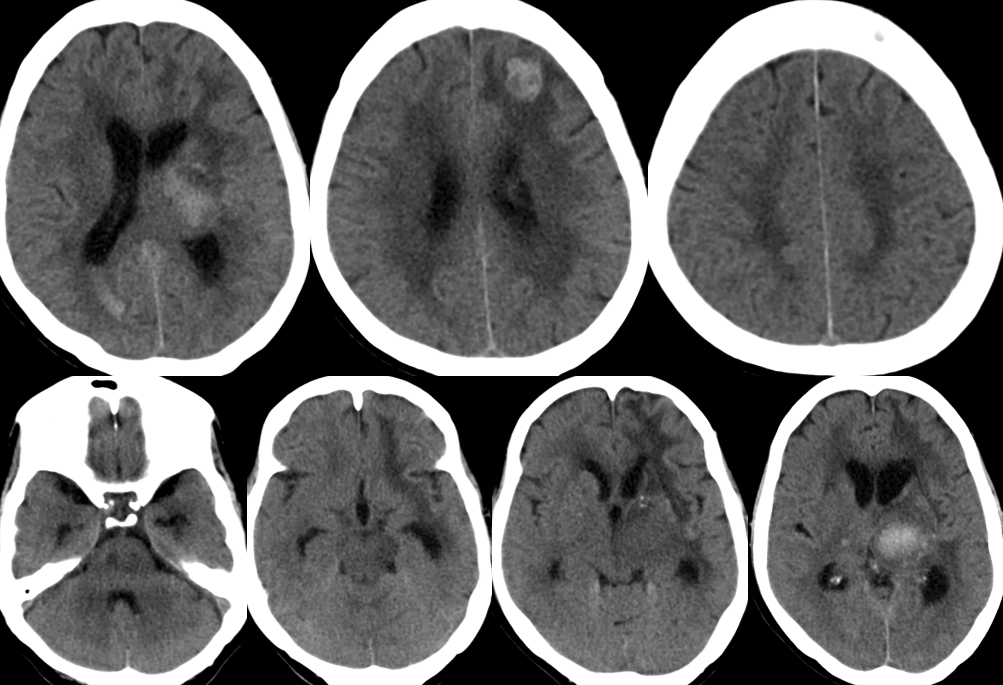

男性反应迟钝10天请诊断

medlive.cn/upload/000/130/626